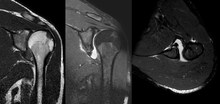

A diagnosis of shoulder dislocation is often suspected based on patient history and physical examination. Radiographs are made to confirm the diagnosis. Most dislocations are apparent on radiographs showing incongruence of the glenohumeral joint. Posterior dislocations may be hard to detect on standard AP radiographs, but are more readily detected on other views. After reduction, radiographs are usually repeated to confirm successful reduction and to detect bony damage. After repeated shoulder dislocations, an MRI scan may be used to assess soft tissue damage. In regards to recurrent dislocations, the supine apprehension test is a useful test in determining athletes who are predisposed to future dislocations.